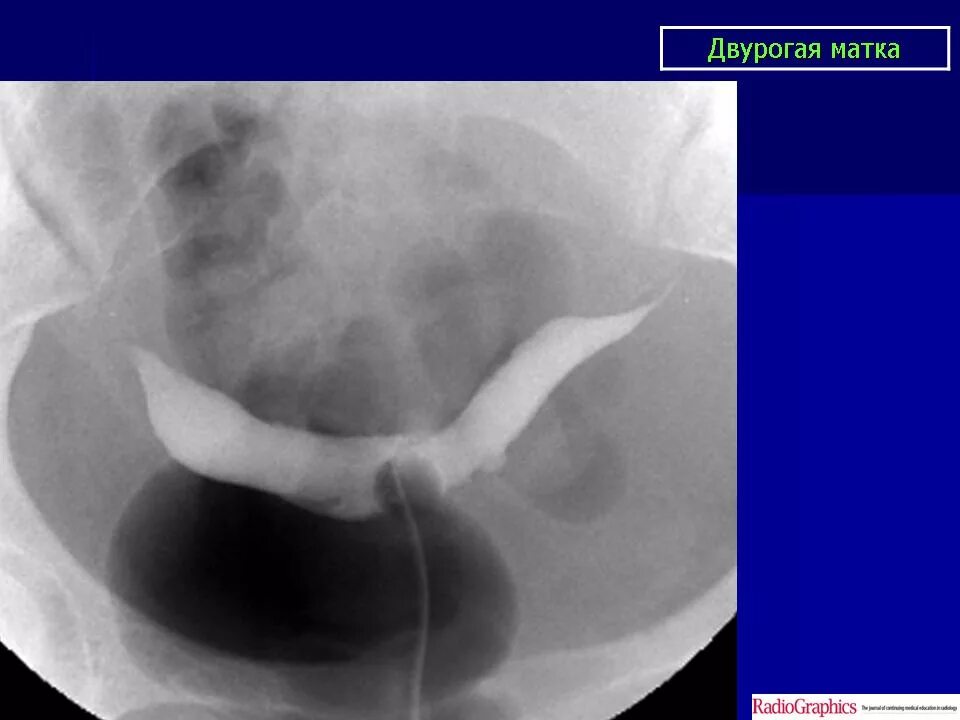

Как выглядят 2 матки